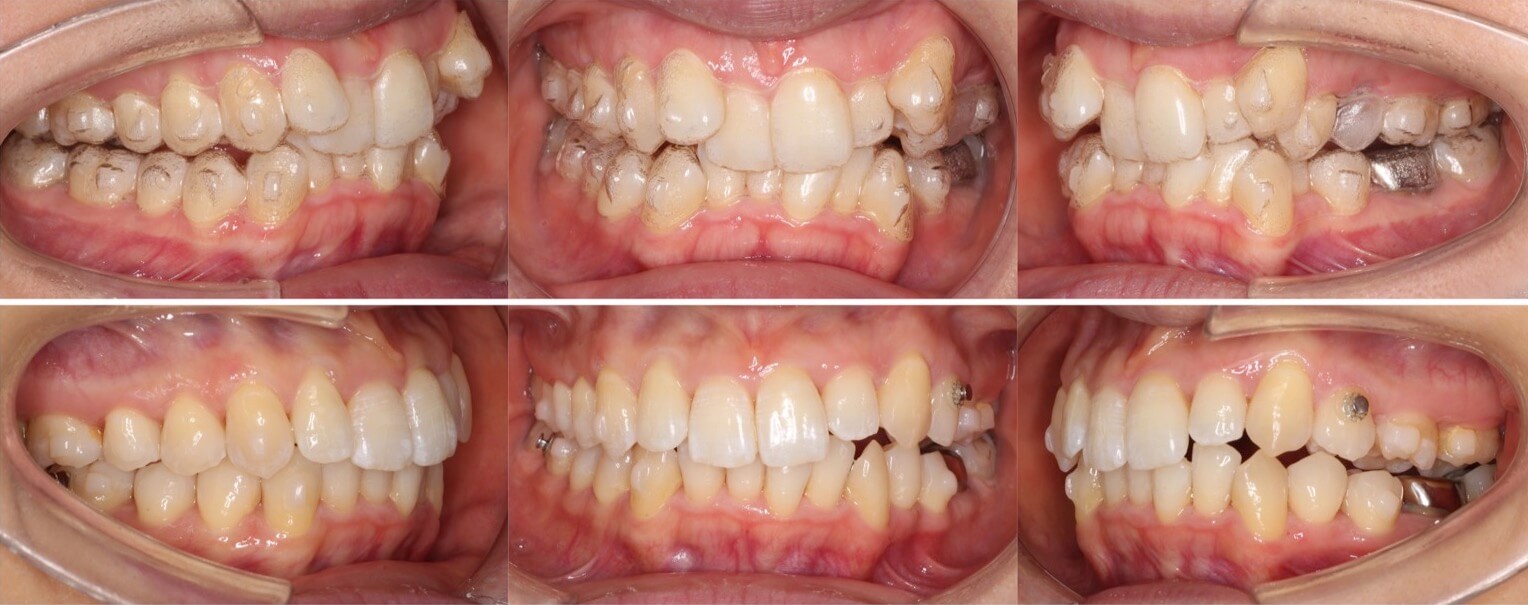

大学生男性・唇側矯正装置・4本抜歯

口元の突出もある重度の過蓋咬合症例は、表側矯正装置の方が確実に治療が可能です。このようなケースの治療期間は3年を超えてしまいます。側方のシザースバイトも併発しているため、下の歯並びにブラケット装置を装着する面積を確保する事に苦戦しました。治療途中は何回もワイヤーが上の歯で噛み切ってしまい折れてしまうため、複雑なワイヤーを併用する事で過蓋咬合を改善しました。

<症例概要>

主訴:口元の突出

年齢・性別:大学生男性

住まい:千葉県八千代市

症状:過蓋咬合・上下顎前突・左側シザースバイト

治療方針:抜歯空隙の閉鎖(最大固定)

治療装置:唇側矯正装置

固定装置:歯科矯正用アンカースクリュー(上頬側x2)

抜歯:上下左右4番(計4本)

治療期間:3年2か月

リテーナー:下フィックスタイプ+上下プレートタイプ

治療費用:968,000(税込)

代表的副作用:痛み・治療後の後戻り・歯根吸収・歯髄壊死・歯肉退縮

▶︎その他の副作用